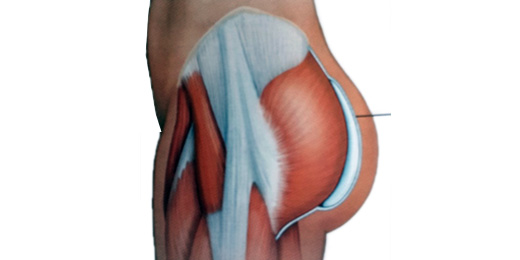

Los planos de colocación que existen son: subcutáneo, subfascial, retromuscular e intramuscular.

El plano subcutáneo presenta un alto índice de complicaciones como seroma, contractura capsular e implante visible y palpable, por lo que no se utiliza actualmente.

El plano subfascial se utiliza en casos seleccionados, que presenten buen panículo adiposo para evitar la visibilidad del implante.

El plano retromuscular es una buena opción, pero permite sólo la inclusión de implantes pequeños, ya que no deben sobrepasar el límite del músculo piramidal para no comprometer el nervio ciático.

El plano intramuscular se considera el más adecuado actualmente, ya que permite cubrir totalmente el implante, pudiéndose utilizar implantes de mayor tamaño y forma anatómica.

Este plano es el que brinda los resultados más naturales.